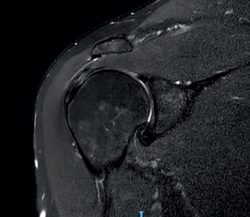

La imagen propia de una tendinosis en RMN es una zona focal o intrasustancia de señal intermedia en T1 que no desaparece en T2 y sin alcanzar la intensidad del fluido en T2 (Figura 6). En ocasiones, se puede observar un engrosamiento difuso o focal del tendón sin evidencia de rotura(33). Una tendinosis puede ser difícil de diferenciar de una rotura parcial en estadio temprano de esta última.

Figura 7. Rotura de espesor parcial bursal del supraespinoso en visión por resonancia magnética nuclear.